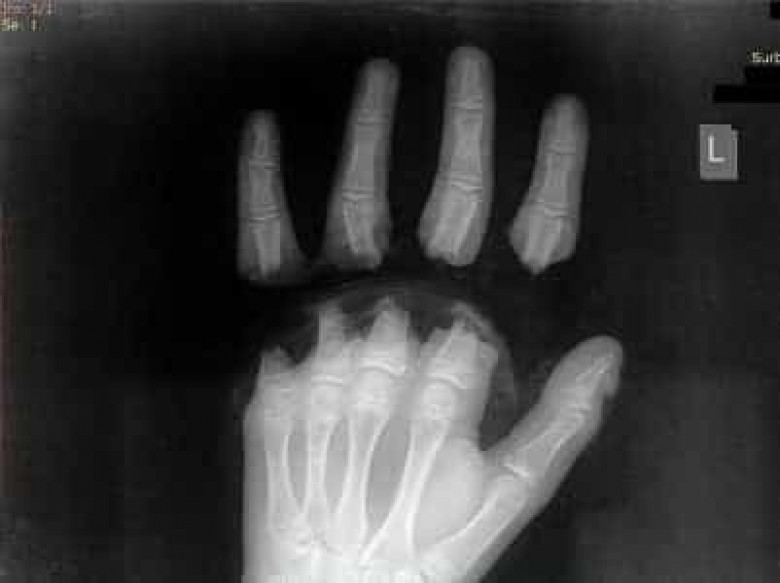

Армянские врачи в ходе десятичасовой операции реплантировали мальчику оторванные пальцы

Армянские врачи в ходе десятичасовой операции реплантировали мальчику оторванные пальцы.

Как сообщил пресс-секретарь МЦ «Сурб Аствацамайр» Геворк Дерцян, в больницу был доставлен 12-летний мальчик с ампутацией 4 пальцев руки.

«Несчастный случай произошел, когда ребенок играл с собакой. На животное вместо поводка был надет стальной трос, другой конец которого мальчик обмотал вокруг пальцев. Собака побежала, трос натянулся и оторвал мальчику пальцы.

Операция продлилась десять часов. Пластические хирурги пришили оторванные пальцы.